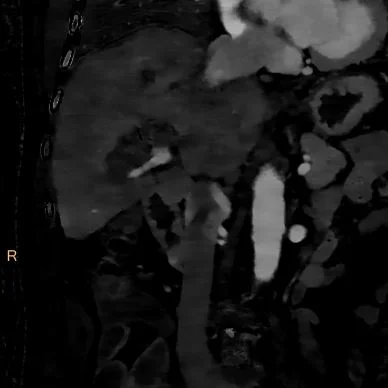

The calculi are confirmed on MRI (T2W coronal image shown). Patient had history of choledochojejunostomy, and multiple biliary procedures in past. Further workup deferred as patient was leaving the country.

T2W coronal MRI confirms calculi, which are without signal (black)